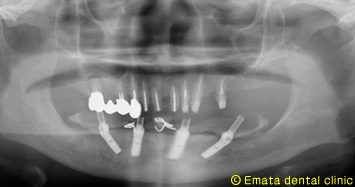

![]() |

CTでシュミレーションを行いました。奥歯には骨がありませんが、前歯の骨がありますので神経までの距離が近いですが、All-on-4の適応症です。 |

下顎神経を避けて、4本のインプラントが綺麗に埋入されています。 |